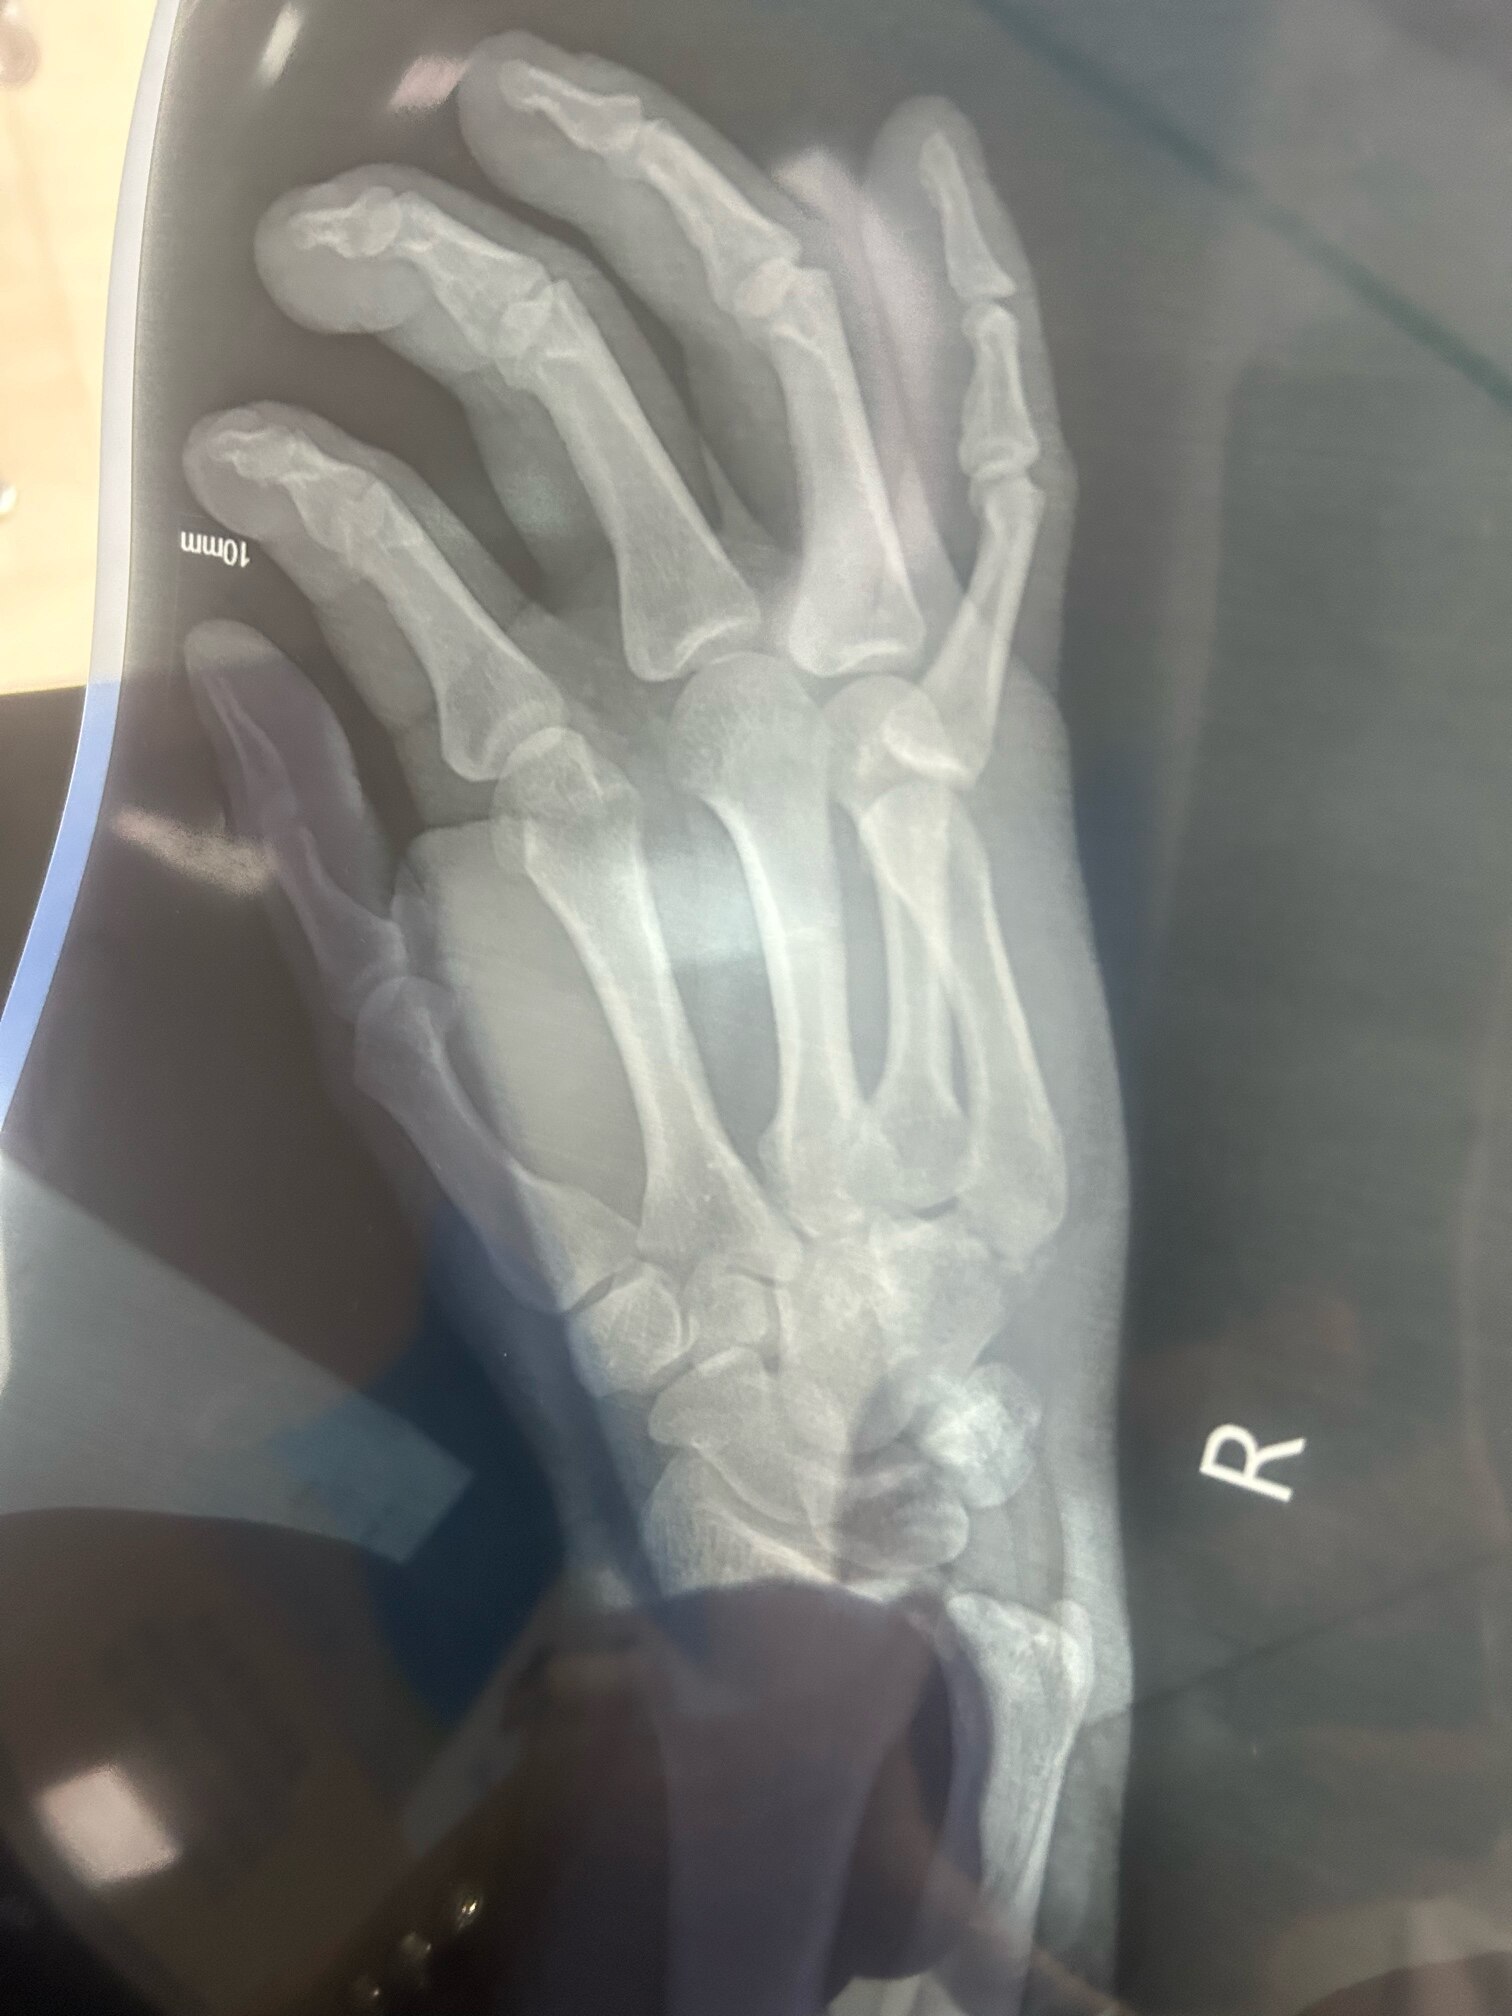

你片都照了,正规医院就有啊。不要相信所谓的江湖医生,要不然,钱花了,还医不好。